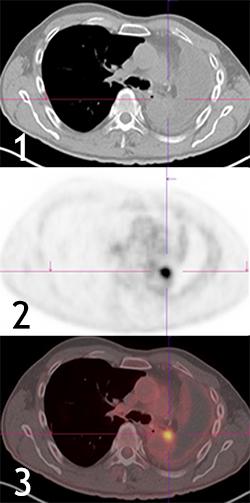

ПЭТ с фтордезоксиглюкозой (ФДГ) и рецидив рака легкого на фоне послеоперационного гидрофиброторакса:

- Изображение КТ;

- Изображение ПЭТ;

- Изображение ПЭТ/КТ